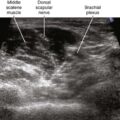

An average heart screening package may include blood pressure, cholesterol, glucose, body mass index, and electrocardiograms (ECG). In other instances, echocardiograms, stress tests, or calcium artery scans may be prescribed. These devices provide a closer look at the heart’s function under various conditions. Both tests are painless and non-invasive; together, they give a better understanding of cardiovascular health.